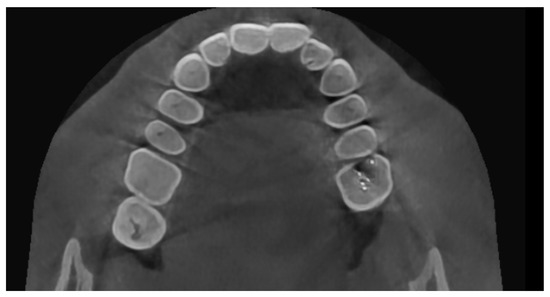

This concept can be explained by a case of swelling in the lower jaw for the past 9 months. No associated pain, numbness, or paresthesia were present. Clinically, distal tipping of 32 and mesial tipping of 33 were evident. Upon vitality testing, 42, 41, 31, and 32 were found to be nonvital. A clinical provisional diagnosis of the radicular cyst was given. The aspiration of the lesion revealed a straw-colored fluid. On CBCT, the pathology in the anterior mandible was evident, with buccal cortical bone destruction, and the internal structure revealed thin septa not extending throughout the lesion (Figure 3a,b). This posed a diagnostic dilemma of either a tumor or a cystic lesion. The gray scale value did not provide insight into the internal structure. The histopathological diagnosis was plexiform ameloblastoma, an odontogenic tumor with centric cystic degeneration.

Figure 3. (a) CBCT images of a clinically diagnosed cystic lesion reveal buccal and lingual cortical bone destruction; (b) Internal structure revealing thin septa that do not extend throughout the lesion. Gray scale value could not differentiate fluid/soft tissue in this case of plexiform ameloblastoma, thus posing a radiological diagnostic dilemma.